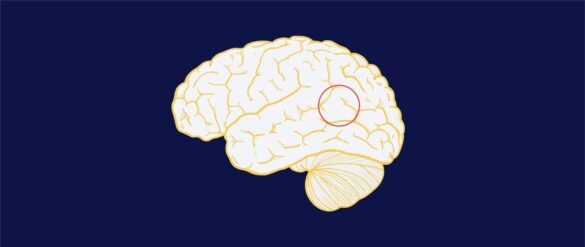

El poder de la unión temporoparietal del cerebro

Puede que el común de la población reconozca, en cierta medida, que las tareas del cerebro son bastante complejas. Sin embargo, hay algunas que son conocidas por involucrarse en muchas funciones. Una de ellas es la unión temporoparietal, una región de asociación supramodal cuyo rol…